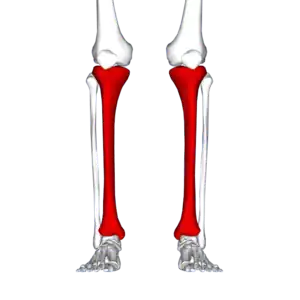

Red area represents the tibia. Pain is generally in the inner and lower 2/3rds of tibia.

A shin splint is pain along the inside edge of the shinbone (tibia) due to inflammation of tissue in the area.[1] Generally this is between the middle of the lower leg to the ankle.[2] The pain may be dull or sharp and is generally brought on by exercise.[1] It generally resolves during periods of rest.[3] Complications may include stress fractures.[2]

Shin splint pain is described as a recurring dull ache, sometimes becoming an intense pain, along the inner part of the lower two-thirds of the tibia.[4] The pain increases during exercise, and some individuals experience swelling in the pain area.[5] In contrast, stress fracture pain is localized to the fracture site.[6]